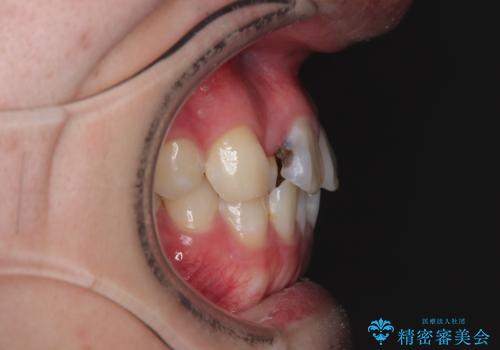

・特に上顎の幅が狭いため、下顎の歯列も内側に入り込み、歯が並ぶスペースが不足していました。

治療方針

このような歯列の狭さに起因するデコボコを改善するために、**MARPE(骨に固定する上顎急速拡大装置)**を使用して、上顎の横幅を拡大し、これにより歯が並ぶためのスペースを確保し、メタルブラケットを用いて歯列を整えていく計画としました。